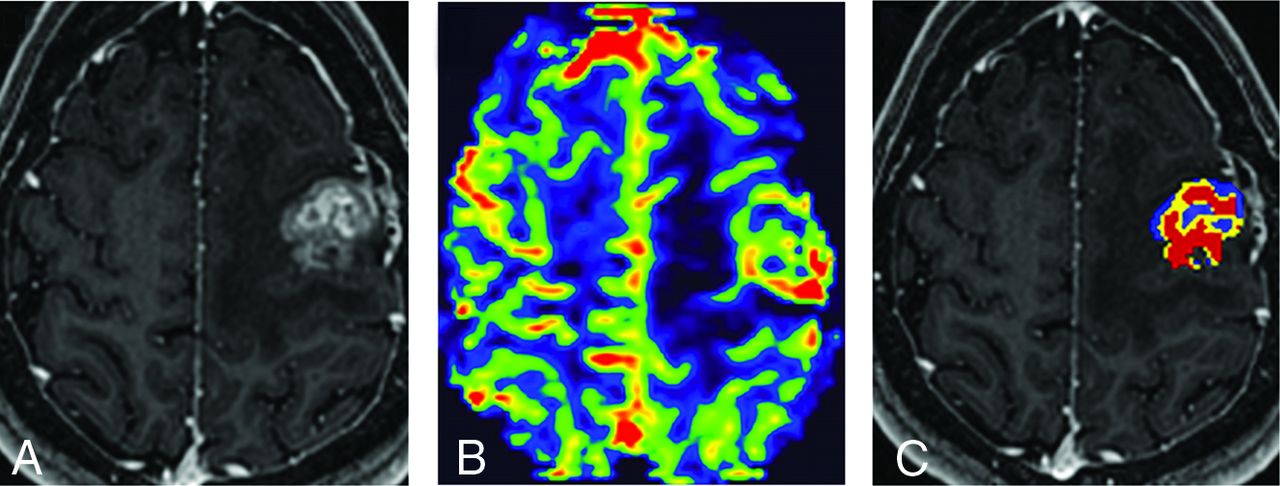

A total of 39 subjects were initially identified. Subjects were excluded if they had nonenhancing lesions (n = 3), extensive susceptibility on raw DSC images (n = 2), and a histopathologic diagnosis of lymphoma or other primary brain tumors (n = 3). One subject was excluded because a clinical assessment of the lesion ground truth could not be made at the time of the study (n =1). After assessment of eligibility, 30 subjects with a total of 37 brain metastases (n = 20 RN, n = 17 tumor) were included in the analysis. All subjects underwent the study perfusion MR imaging, comprising DSC (n = 30), DCE (n = 26), and ASL (n = 26). A subset of 17 subjects with 20 total lesions (n = 8 RN, n = 12 tumor) underwent FDG-PET MR imaging. Table 1 summarizes the demographics and clinicopathologic information. Figures 1 and 2 demonstrate representative DSC imaging performed in subjects with RN and tumor, respectively.

RN in a 58-year-old man with metastatic colon cancer presenting 17 months after surgical resection of a right parietal metastasis treated with SRS. A, Recurrent contrast-enhancing lesion at the site of the original tumor on axial T1-weighted postcontrast image. On DSC, the masslike lesion shows low RCBV (B) and predominantly FTBlow (blue) voxels (C). Low perfusion is consistent with pathology-proved RN (with <5% viable tumor cells).

Progressive tumor in a 33-year-old woman with breast cancer presenting 8 months after surgical resection of a left frontal metastasis treated with stereotactic radiosurgery. A, A recurrent contrast-enhancing lesion at the site of the original tumor on an axial T1-weighted postcontrast image. On DSC, the masslike lesion shows high RCBV (B) and predominantly FTBhigh (red) voxels (C). High perfusion is consistent with pathology-proved progressive tumor.